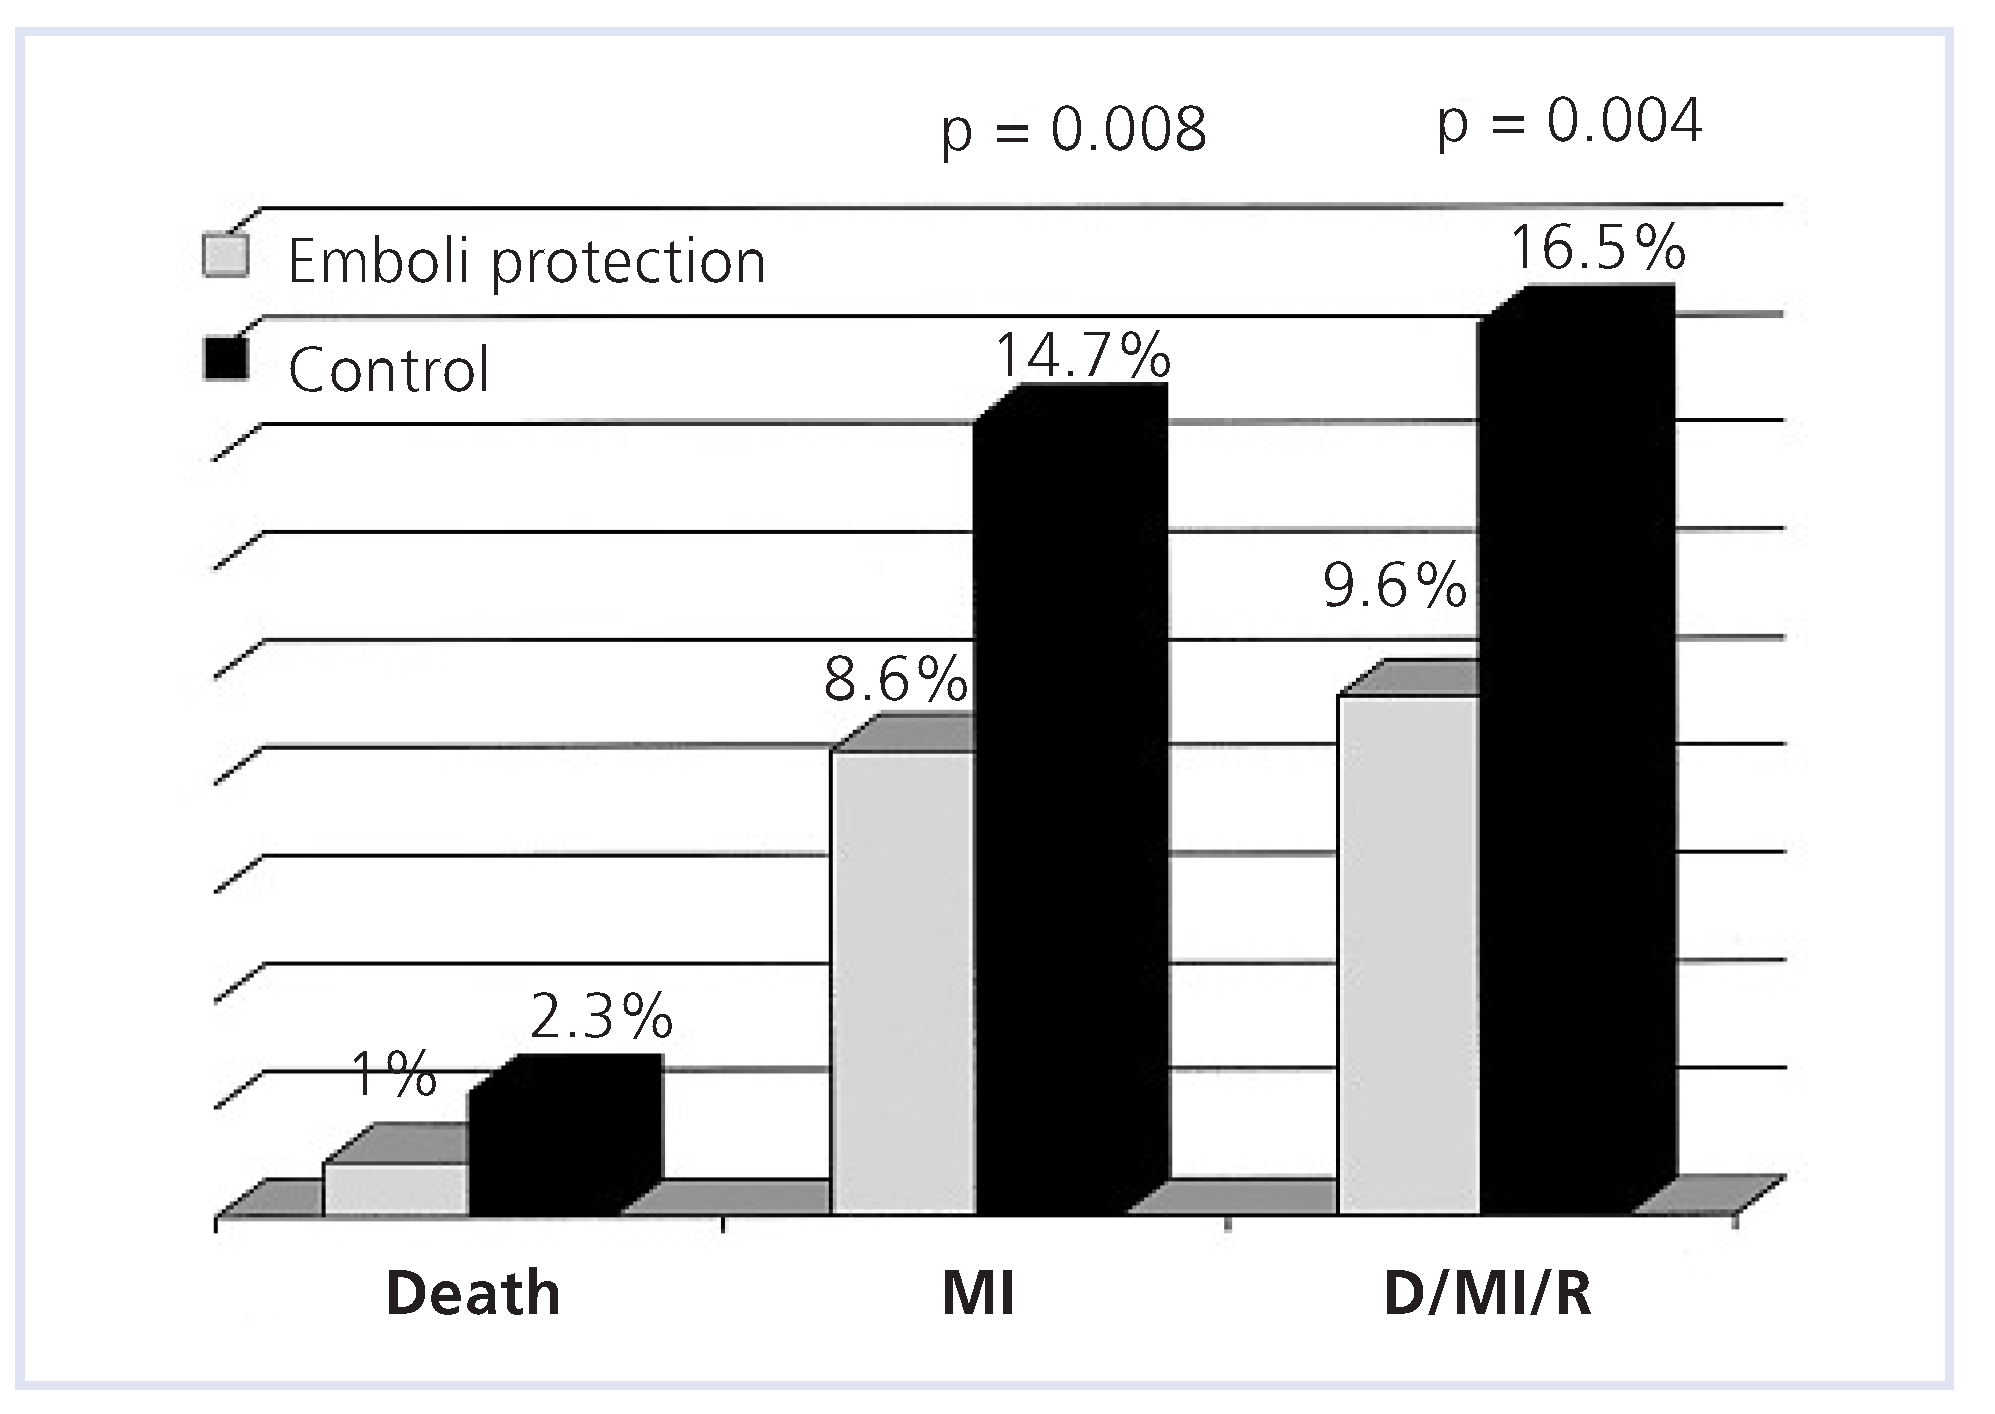

Aortocoronary bypass grafts interventions

- Baim, D.S.; Wahr, D.; George, B.; Leon, M.B.; Greenberg, J.; Cutlip, D.E.; et al. Randomized trial of a distal embolic protection device during percutaneous intervention of saphenous vein aorto-coronary bypass grafts. Circulation. 2002, 105, 1285–1290. [Google Scholar]

- Stone, G.W.; Rogers, C.; Hermiller, J.; Feldman, R.; Hall, P.; Haber, R.; et al. Randomized comparison of distal protection with a filter-based catheter and a balloon occlusion and aspiration system during percutaneous intervention of diseased saphenous vein aorto-coronary bypass grafts. Circulation. 2003, 108, 548–553. [Google Scholar] [PubMed]

- Mauri, L.; Cox, D.; Hermiller, J.; Massaro, J.; Wahr, J.; Tay, S.W.; et al. The PROXIMAL trial: proximal protection during saphenous vein graft intervention using the Proxis Embolic Protection System: a randomized, prospective, multicenter clinical trial. J Am Coll Cardiol. 2007, 50, 1442–1449. [Google Scholar]

- Mehta, S.K.; Frutkin, A.D.; Milford-Beland, S.; Klein, L.W.; Shaw, R.E.; Weintraub, W.S.; et al. Utilization of distal embolic protection in saphenous vein graft interventions (an analysis of 19,546 patients in the American College of Cardiology-National Cardiovascular Data Registry). Am J Cardiol. 2007, 100, 1114–1118. [Google Scholar]